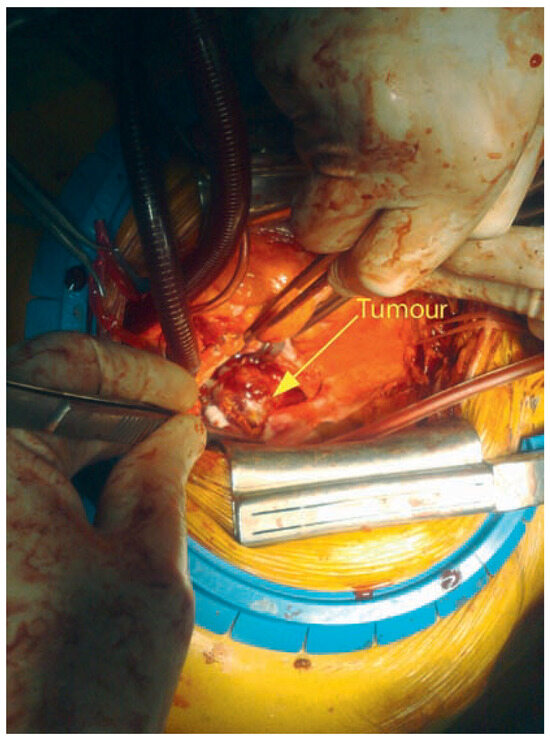

Interesting Images

Benign Left Atrial Glomangiopericytoma

by Michel Grobéty, Gregory Katchatourov, François Perret, Stephan Schäfer and Jean-Jacques Goy

Cardiovasc. Med. 2008, 11(9), 288; https://doi.org/10.4414/cvm.2008.01347 (registering DOI) - 26 Sep 2008

Cited by 1 | Viewed by 100

Abstract

Case report This 47-year-old woman had a history of Hodgkin disease treated with chemotherapy and irradiation at the age of seventeen [...] Full article

Show Figures

Figure 1